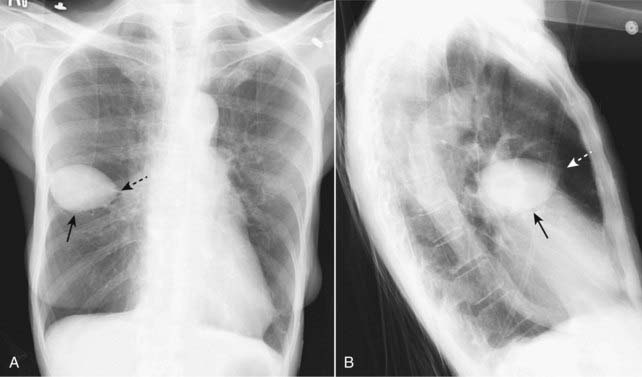

Figure 6-12 Pseudotumor in the minor fissure, frontal (A) and lateral (B) projection.

A sharply marginated collection of pleural fluid contained between the layers of the minor fissure produces a characteristic lenticular shape (solid black arrows in A and B) that frequently has pointed ends on each side where it insinuates into the fissure so that pseudotumors look like a lemon on frontal (A) or lateral (B) chest radiographs (dotted black arrow on A and dotted white arrow on B). Pseudotumors almost always occur in patients with congestive heart failure and, although the pseudotumors disappear when the underlying condition is treated, they frequently return each time the patient’s failure recurs.